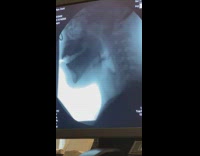

Collab SendItOfficiall - Man rides mini bike breaks his bone

Just a dumb jump over a lil pool riding a mini motorcycle and breaking his clavicle bone on his shoulder seen at the x-ray result